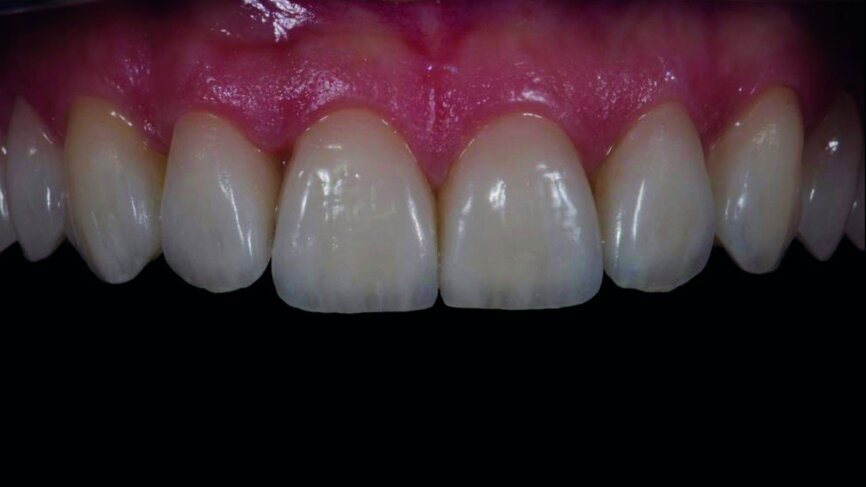

Fig. 17a: Final outcome one week later.

Fig. 17b: Final outcome one week later, frontal view.

The subjective decision of the clinician and the patient was to cement the feldspathic veneers, owing to slight differences in the length of the central incisors between the two sets. Adhesive procedures followed (Figs. 16a–f), and final intraoral and extraoral photographs were captured one week later (Figs. 17a–e).

Intraoral digital scanning is a perfect alternative clinical procedure compared with the conventional impression technique. The digital planning and mock-up procedure is a powerful communication tool for the dentist, although special skills in using computer software are required. Regarding the laboratory workflow, most of the analogue procedures require more time (refractory dies, built-up veneers, adjustments), except the staining/glazing (Figs. 18a & b). Although the aesthetic outcome of the feldspathic veneers was subjectively chosen in this case, the analogue workflow is much more demanding. The digital approach, because of the reduced difficulty, speed, complexity and patient discomfort, tends to be preferable (Figs. 18a & b).